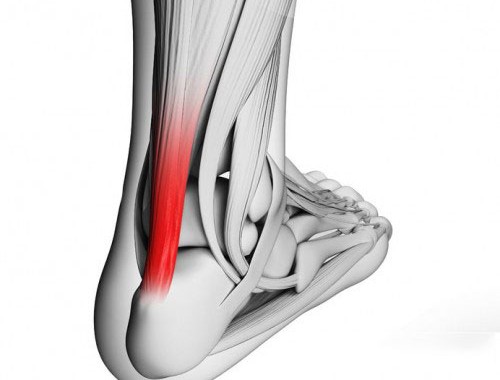

Cuando los tendones se insertan en el esqueleto, su terminación se caracteriza por una fusión íntima con el periostio, que es la membrana que recubre la superficie externa de los huesos. Aunque las fibras tendinosas no penetran directamente en el hueso, la tracción ejercida por el tendón en la superficie de inserción puede provocar la aparición de salientes óseas, procesos o espinas. Estas adaptaciones óseas son una respuesta a la tensión mecánica y el estrés a los que se somete el hueso debido a la tracción del tendón. Ejemplos de esto incluyen el tendón calcáneo (tendón de Aquiles) que se inserta en el hueso del talón y el tendón del iliopsoas que se inserta en el fémur.